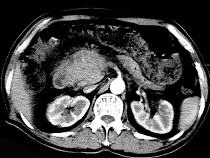

问题 男,50岁,黄疸进行性加重、腹部胀痛不适、食欲减退、体重减轻、上腹部可触及肿块,CT如图,最可能的诊断为()

选项 A.急性胰腺炎 B.慢性胰腺炎 C.胰头癌 D.腹膜后淋巴瘤 E.转移瘤

答案 C